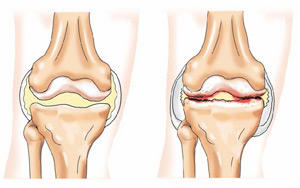

Артроз — это разрушение хрящевой ткани. Она истончается, расслаивается, в ней появляются трещины, в результате кость, находящаяся под хрящом обнажается, на ней появляются уплотнения, которые со временем разрастаются, превращаясь в шипы. Происходит деформация сустава. Человеку, страдающему артрозом коленного сустава, каждый шаг доставляет боль.

Можно сказать, что при этом заболевании суставной хрящ растрескивается, становится тоньше, теряя при этом свою волокнистость и амортизационные свойства, что, в принципе, не дает возможности во время движения смягчать периодические удары коленного сустава и тела.

Остеоартроз – это дегенеративное заболевание. Под нагрузкой, особенно если еще нарушен обмен веществ, изменяется питание хряща, покрывающего внутрисуставные поверхности костей. На хряще появляются трещины, он фрагментируется, разрушается, это сопровождается воспалением. Постепенно, если не лечиться, участки подлежащей кости теряют хрящевой покров, что приводит к механическому раздражению костной ткани, ее уплотнению, появлению костных разрастаний – остеофитов. Все это человек ощущает как боль, усиливающуюся при нагрузке на сустав, скованность, ограничение движений. Больному деформирующим остеоартрозом становится тяжело ходить, выполнять ежедневную работу. На рентгенограмме наблюдается неравномерное сужение суставной щели, кисты и остеофиты. Возможна и полная утрата суставного хряща, а соответственно, и обездвижение сустава. Стоит помнить, что остеоартроз – это не отложение солей, как принято говорить в народе, это разрушительный процесс, начинающийся с хрящевой ткани.

По мере прогрессирования болезни, когда хрящевая ткань полностью разрушена, организму ничего не остается, как начинать защищаться. Это проявляется разрастанием костной ткани на костях, формирующих сустав в виде «шипов» (остеофитов), возникает деформирующий артроз коленного сустава. В суставных полостях появляется эксудат.